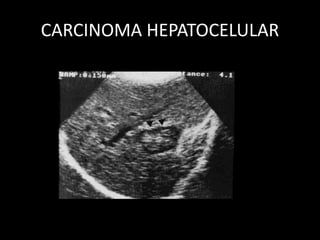

TUMORES HEPATICOS MALIGNOS:

HEPATOCARCINOMA

• Masa compleja: Ecorrefrigencia irregular.

• Áreas de necrosis y calcificaciones.

• Estrías lineales dentro de las venas, luego trombosis

• Invade los conductos intrahepaticos, originando dilataciones

dístales

• Dilatación de la vena cava inferior y de la arteria hepática

• Hipervascularizado.

• Ganglios regionales

• Metástasis a distancia

CARCINOMA HEPATOCELULAR

• - La más frecuente es el hepatocarcinoma,

que suele asentar sobre un hígado con una

hepatopatía de base.

• - Puede infiltrar e! hígado de forma difusa,

o bien presentarse como una lesión focal.

Imagen hipodensa en la TC en la

mayor parte de los casos aunque un

pequeño porcentaje son isodensos,

lo que conlleva serios problemas

diagnósticos.

Son tumores que se vascularizan a partir de la

arteria hepática, por lo que en los primeros

segundos que siguen a la inyección rápida (en

forma de bolo) de contraste intravenoso

suelen captar intensamente .

Con frecuencia producen infiltración

vascular (trombosis portal tumoral) y

dan metástasis en otras localizaciones

hepáticas.